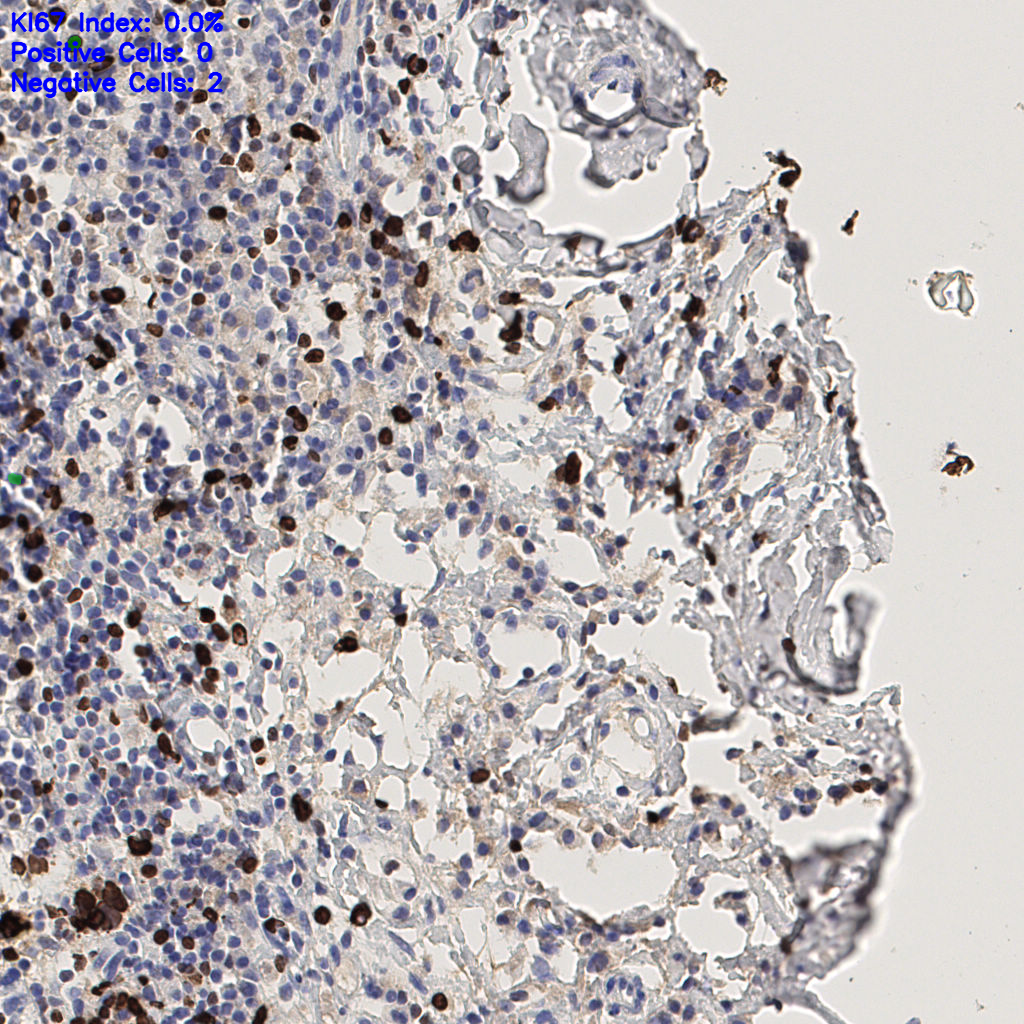

7.85%

Ki67 指数

阴 1104 阳 94

H255858-KI-67.ndpi

slice_44_4_x39424_y3584.png

slice_44_4_x39424...